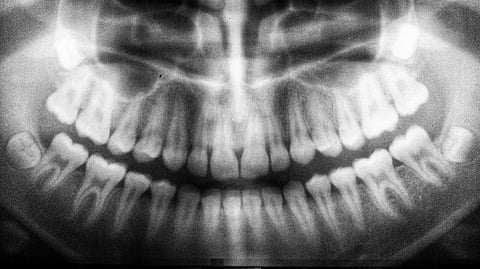

Since dental X-rays became commonplace some seven decades ago, dentists and hygienists have been draping their patients with protective gear to shield them from the possibility of radiation exposure to body parts other than the jaw. But experts in dental radiology say it’s time to hang up those lead aprons for good.

The digital radiograph equipment used in dental offices today is lightyears away from that of past generations, and the amount of external radiation scatter, as it’s known, from modern X-ray technology poses little to no threat to patients, according to the American Academy of Oral and Maxillofacial Radiology (AAOMR). The organization has recommended that lead aprons and thyroid shields do not need to be used routinely for dental X-rays.

The negligible radiation exposure a dental patient receives to areas away from the head comes through “internal scatter,” in which a small amount of the radiation that enters through the head and neck, the area targeted by the X-ray machine, bounces to other parts of the body, Ramesh says. “The internal scatter that exposes the organs below the jaw cannot be prevented with an apron.”

In fact, Ramesh says, it’s possible an apron or collar can interfere with getting a clear shot of the jaw, making it necessary to try a second time, doubling the overall dose. “Preserving the quality of the images is the best way we have of protecting our patients,” says Hugo Campos, associate professor and director of oral and maxillofacial radiology at TUSDM.